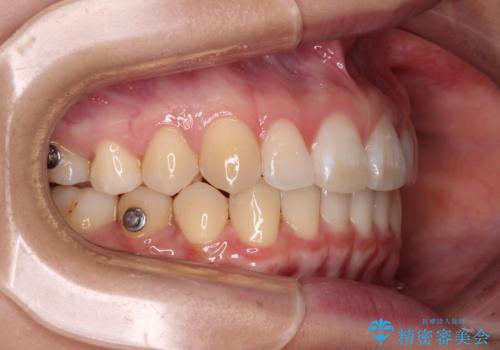

- 上顎前歯の隙間を気にして来院された患者様です。

下顎前歯が上顎前歯に食い込むような咬み合わせにより、上顎前歯が開いてしまっていたため、咬合高径の挙上により突き上げを改善するよう、インビザラインにより矯正治療を行うこととしました。

咬合高径の挙上により上顎前歯の突出感も改善することができ、整った口元となりました。